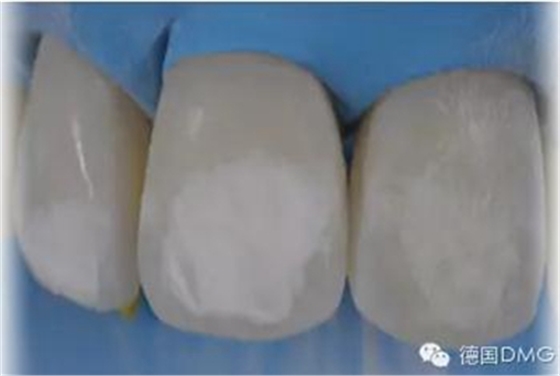

5、由于氟斑牙存在釉質(zhì)礦化不全等問題,家庭漂白兩周后,使用標(biāo)準(zhǔn)的樹脂滲透技術(shù) (Icon, DMG Products, Hamburg. Germany) 來預(yù)防釉質(zhì)齲。最后,徹底改變患者的前牙美學(xué),并在一年后仍保持穩(wěn)定

利用樹脂滲透技術(shù)治療重度氟斑牙是一項(xiàng)新技術(shù)。采用這一技術(shù),主要同氟斑牙結(jié)構(gòu)和樹脂性質(zhì)有關(guān)。一般來說,氟斑牙釉質(zhì)深層存在彌散的礦化不全和多孔結(jié)構(gòu)。當(dāng)表層氟化的釉質(zhì)通過粗打磨和微打磨磨除后,深層礦化不全的釉質(zhì)暴露在口腔環(huán)境中,其多孔結(jié)構(gòu)為細(xì)菌和酸提供了通道。

因滲透性樹脂有極低的粘性、與釉質(zhì)的接觸角低且表面張力高,其可以穿透并封閉釉質(zhì)中的通道。而且,因其與釉質(zhì)有相似的折射率,樹脂滲漏可以改變孔隙的白堊色外觀,并減少孔隙和釉質(zhì)對(duì)光線散射的差異,進(jìn)而導(dǎo)致釉質(zhì)顏色的改變。